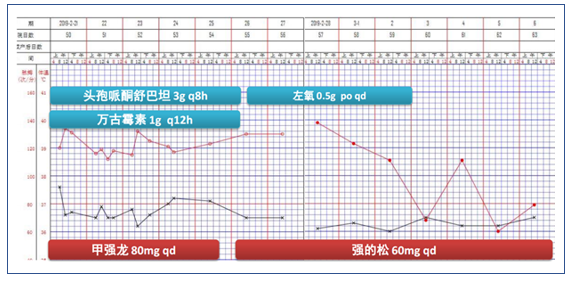

图3 患者初始治疗方案及生命体征变化情况

根据患者临床表现及检查结果,再次调整治疗方案(图10)。